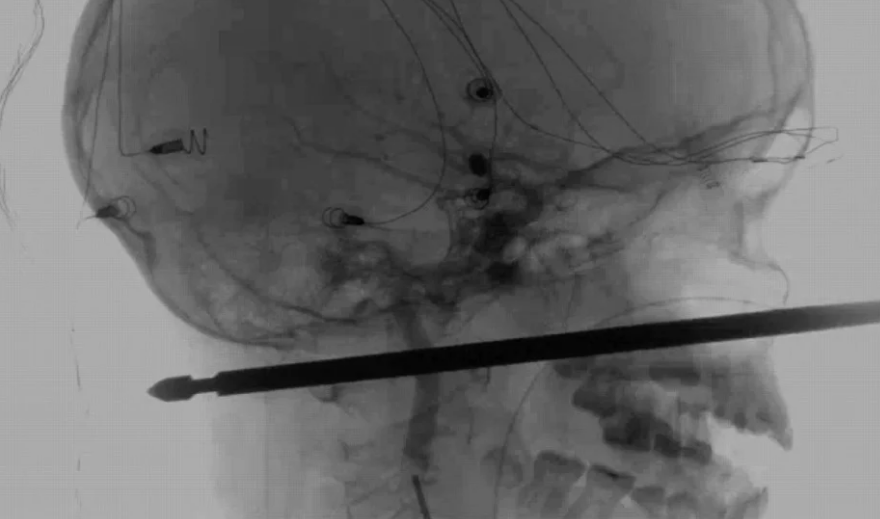

Mặc dù khoảng cách từ bậc thang xuống đất không cao, chỉ khoảng 1,2 m nhưng nơi cậu bé 10 tuổi ngã xuống lại đang có một cây xiên thịt dài 30 cm chĩa mũi nhọn lên trên. Cây xiên thịt đâm vào mặt Xavier, ngay phía dưới mắt và chạm đến vùng da sau gáy. Nhưng may thay, thanh xiên thịt không đâm vào hộp sọ và não của Xavier.

“Cây xiên không đâm trúng não thằng bé cũng không đâm trúng dây thần kinh hay bất kỳ bộ phận nhạy cảm nào trong đầu. Nó trượt qua mọi thứ”, ông Shannon chia sẻ. Bà Gabrielle Miller, mẹ của bé Xavier nói: “Tôi nghe thấy tiếng la hét. Sau đó, con trai tôi bước vào nhà với một thanh sắt trên mặt“.

Cây xiên thịt đâm xuyên qua đầu cậu bé 10 tuổi.

Ngay sau tai nạn hy hữu, Xavier được đưa tới Bệnh viện Đại học Kansas để chữa trị. Xavier đã trải qua một cuộc phẫu thuật vào ngày 9/9 để lấy cây xiên ra khỏi đầu. Ca phẫu thuật diễn ra thành công và cậu bé đang dần hồi phục. Một ngày sau phẫu thuật, Xavier đã tỉnh dậy và có thể nói chuyện với mọi người.

Nhà thần kinh học Koji Ebersole chia sẻ: “Tôi chưa từng thấy trường hợp nào bị đâm sâu như vậy mà vẫn có thể sống sót“. Ông cũng cho biết, có khoảng 100 bác sĩ tham gia vào ca phẫu thuật này. Sở dĩ các bác sĩ để qua ngày sau mới phẫu thuật là để họ có thời gian chuẩn bị thiết bị y tế cần thiết cũng như duy trì tinh thần tỉnh táo nhất.